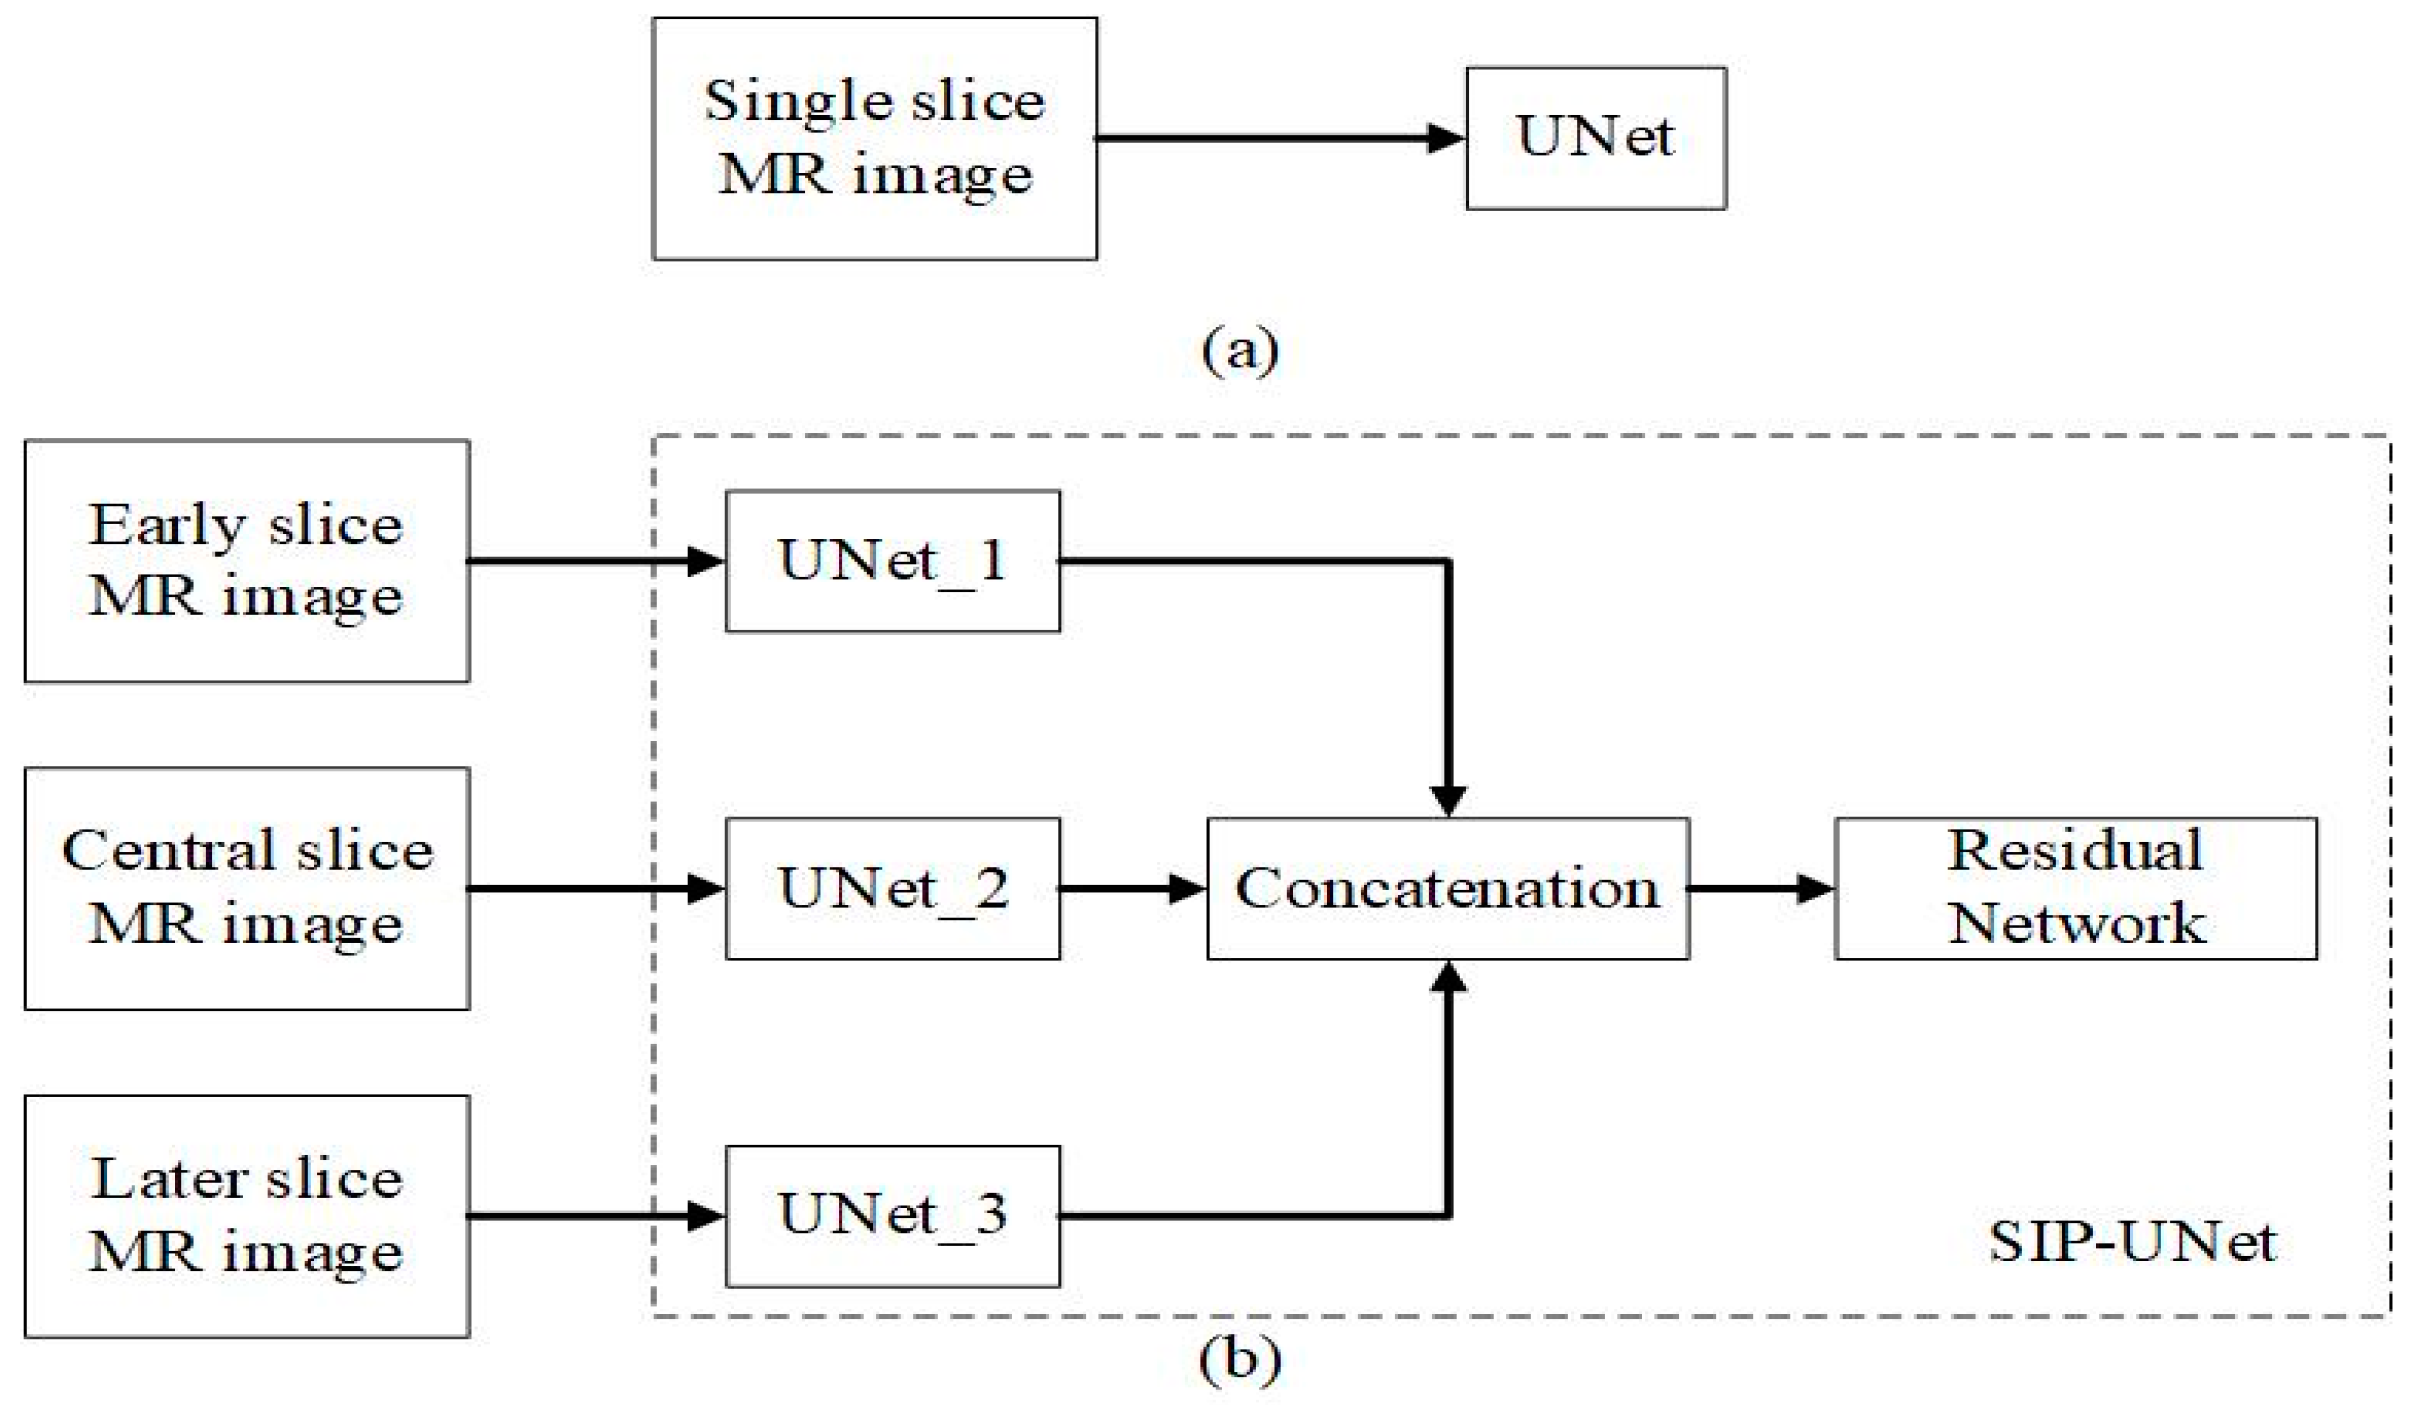

2.2.1. Parallel UNet

| Layer Name | Output Shape | Connected to |

|---|---|---|

| Input_1 | 256 × 256 × 1 | |

| Conv2d | 256 × 256 × 32 | Input_1 |

| Conv2d_1 | 256 × 256 × 32 | Conv2d |

| Max_pooling2d | 128 × 128 × 32 | Conv2d_1 |

| Conv2d_2 | 128 × 128 × 64 | Max_pooling2d |

| Conv2d_3 | 128 × 128 × 64 | Conv2d_2 |

| Max_pooling2d_1 | 64 × 64 × 64 | Conv2d_3 |

| Conv2d_4 | 64 × 64 × 128 | Max_pooling2d_1 |

| Conv2d_5 | 64 × 64 × 128 | Conv2d_4 |

| Max_pooling2d_2 | 32 × 32 × 128 | Conv2d_5 |

| Conv2d_6 | 32 × 32 × 256 | Max_pooling2d_2 |

| Conv2d_7 | 32 × 32 × 256 | Conv2d_6 |

| Max_pooling2d_3 | 16 × 16 × 256 | Conv2d_7 |

| Conv2d_8 | 16 × 16 × 512 | Max_pooling2d_3 |

| Conv2d_9 | 16 × 16 × 512 | Conv2d_8 |

| Conv2d_transpose | 32 × 32 × 256 | Conv2d_9 |

| Concatenate | 32 × 32 × 512 | Conv2d_transpose, Conv2d_7 |

| Conv2d_10 | 32 × 32 × 256 | Concatenate |

| Conv2d_11 | 32 × 32 × 256 | Conv2d_10 |

| Conv2d_transpose_1 | 64 × 64 × 128 | Conv2d_11 |

| Concatenate_1 | 64 × 64 × 256 | Conv2d_transpose_1, Conv2d_5 |

| Conv2d_12 | 64 × 64 × 128 | Concatenate_1 |

| Conv2d_13 | 64 × 64 × 128 | Conv2d_12 |

| Conv2d_transpose_2 | 128 × 128 × 64 | Conv2d_13 |

| Concatenate_2 | 128 × 128 × 128 | Conv2d_transpose_2, Conv2d_3 |

| Conv2d_14 | 128 × 128 × 64 | Concatenate_2 |

| Conv2d_15 | 128 × 128 × 64 | Conv2d_14 |

| Conv2d_transpose_3 | 256 × 256 × 32 | Conv2d_15 |

| Concatenate_3 | 256 × 256 × 64 | Conv2d_transpose_3, Conv2d_1 |

| Conv2d_16 | 256 × 256 × 32 | Concatenate_3 |

| Conv2d_17 | 256 × 256 × 32 | Conv2d_16 |

| Conv2d_18 | 256 × 256 × 4 | Conv2d_17 |